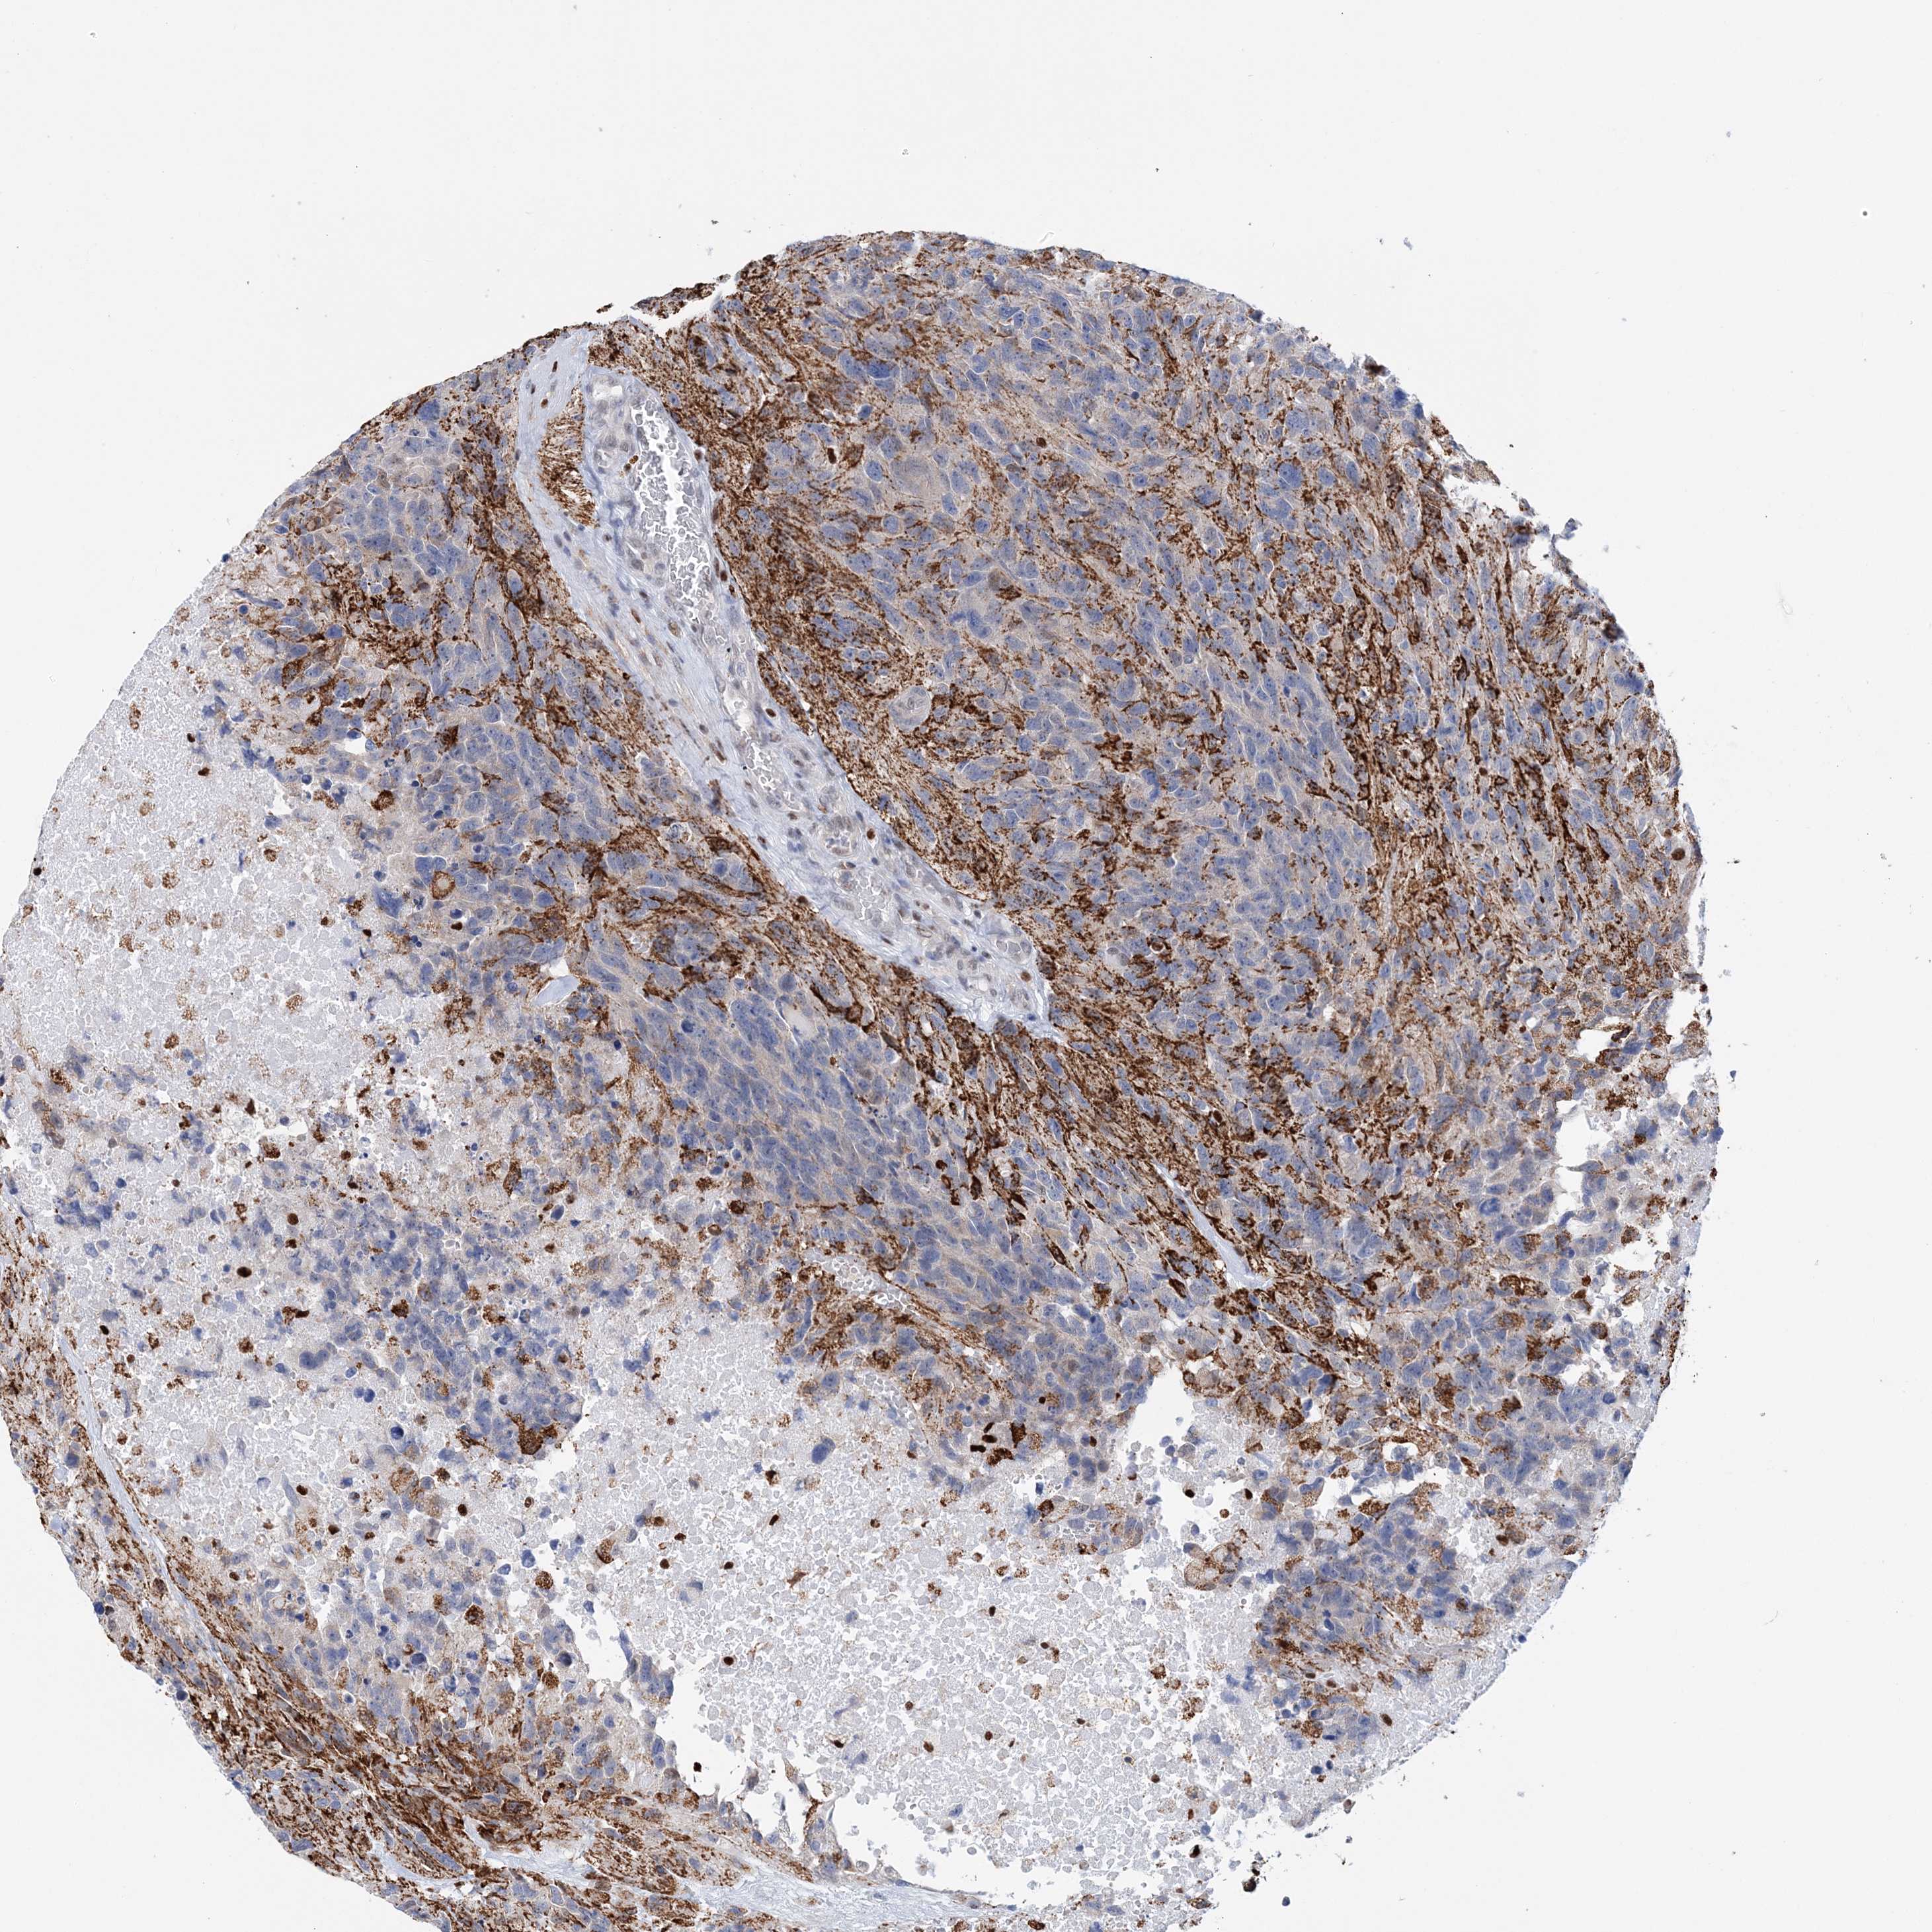

GLIOMA - Protein expressioni

A mouse-over function shows sample information and annotation data. Click on an image to view it in a full screen mode. Samples can be filtered based on level of antibody staining by selecting one or several of the following categories: high, medium, low and not detected. The assay and annotation is described here.

Note that samples used for immunohistochemistry by the Human Protein Atlas do not correspond to samples in the TCGA dataset.

Antibody stainingi

Antibody staining in the annotated cell types in the current human tissue is reported as not detected, low, medium, or high, based on conventional immunohistochemistry profiling in selected tissues. This score is based on the combination of the staining intensity and fraction of stained cells.

Each image is clickable and will lead to virtual microscopy that enables deeper exploration of all samples and also displays staining intensity scores, fraction scores and subcellular localization as well as patient and tissue information for each sample.

Antibody HPA036999

Antibody HPA041289

Staining

High

Medium

Low

Not detected

Intensity

Strong

Moderate

Weak

Negative

Quantity

>75%

75%-25%

<25%

None

Location

Nuclear

Cytoplasmic/membranous

Cytoplasmic/membranous,nuclear

Glioma, malignant, High grade

Glioma, malignant, Low grade

Glioblastoma, NOS